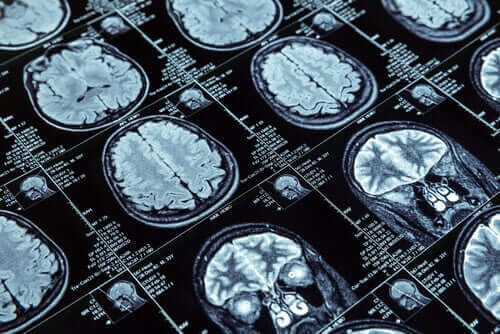

Para desenvolver a pesquisa, uma ressonância nuclear magnética foi realizada em mais de 600 pessoas com 45 anos de idade no momento do teste de imagem. Essas 600 pessoas fazem parte de um grupo maior, de mais de mil, que os neozelandeses monitoram desde a infância.

Nas ressonâncias realizadas nos participantes da pesquisa, foi medida a espessura do córtex cerebral e a quantidade de substância cinzenta que possuíam. Esses dados permitiriam uma comparação entre aqueles com comportamentos antissociais e aqueles que não os possuem.

Resultados significativos foram encontrados no primeiro grupo. As ressonâncias magnéticas cerebrais dessas pessoas mostraram um encolhimento do córtex cerebral em comparação com as outras, além de uma quantidade um pouco menor de substância cinzenta.

O que é evidente é a mudança na arquitetura cerebral que um pequeno grupo da população pode ter em relação aos comportamentos antissociais. Essas mudanças poderiam explicar a personalidade antissocial que se manifesta persistentemente ao longo dos anos.